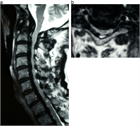

1. 脊柱変形、骨破壊の強い例では、インスツルメンテーションを併用した後方固定を除圧術に併用する。

1. 透析脊椎症の重症度以上に、全身合併症の重症度評価が手術適応、術式選択に際して重要。